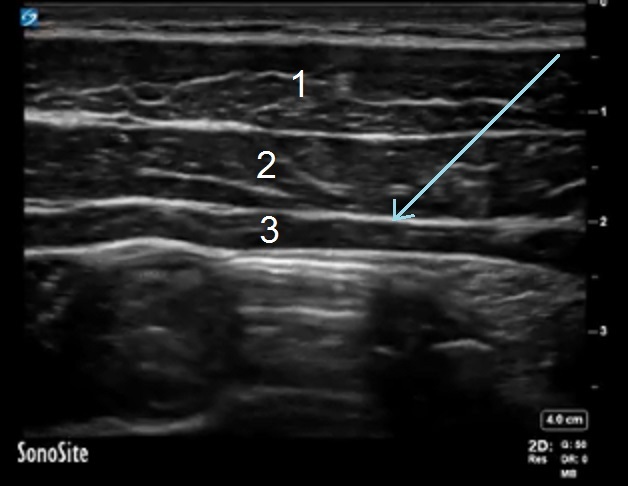

TAP Three Muscle Layers Image

1. External Oblique Muscle

2. Internal Oblique Muscle

3. Transversus Abdominis Muscle

Blue Arrow: Fascia